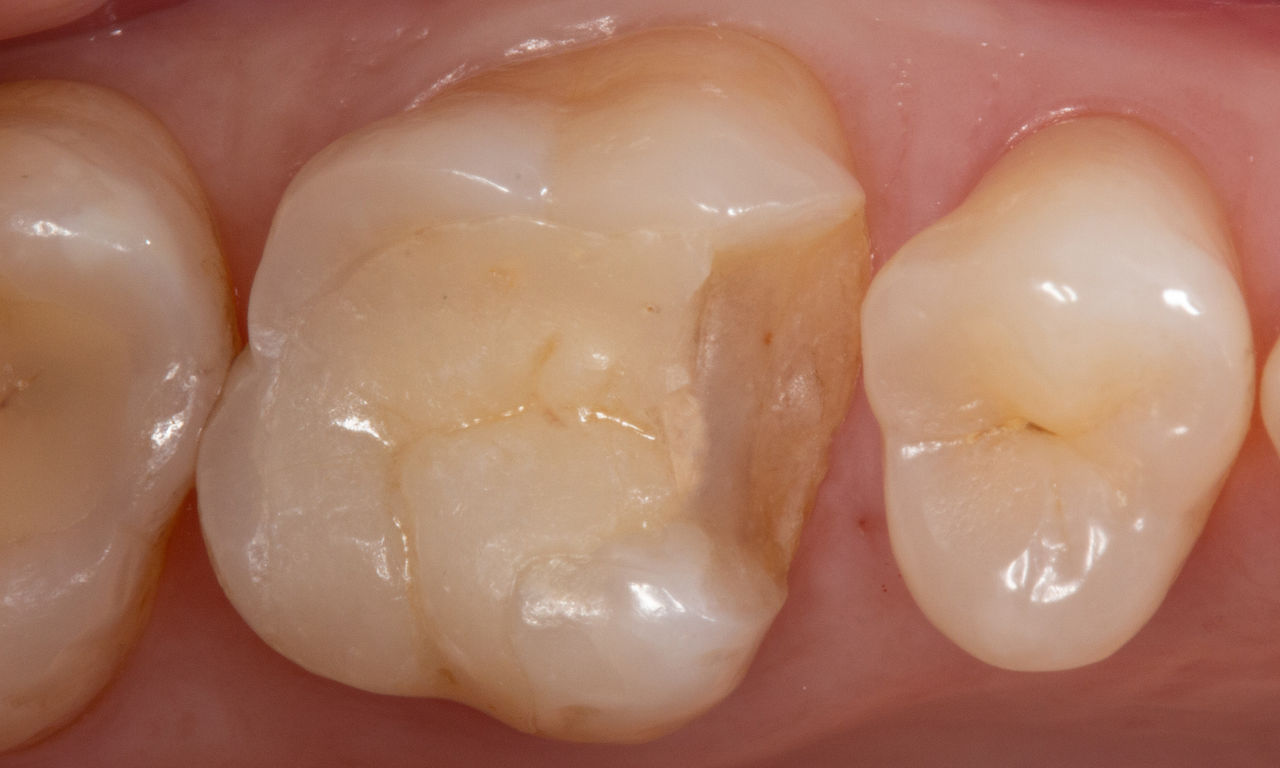

Klinikte alt ikinci molar restorasyonu

Kısmi CEREC Tessera kuronu

Bukkal yüzeyde kapsamlı bir Sınıf I kompozit restorasyonun yanı sıra çatlaklarla birlikte, hassas alt ikinci molar. Minimal invazif konsepte göre, tek bir ziyarette CEREC Tessera kullanılarak CAD/CAM kısmi kuron planlandı, imal edildi ve bağlandı.

Önce: Değiştirme gerektiren başarısız amalgam restorasyonu. Hasta hassasiyetten şikayet ediyor ve dişte birden fazla çatlak bulunuyor.

Sonra: Klinikte, CEREC Tessera Gelişmiş Lityum-Disilikat cam seramikten imal edilmiş CAD/CAM kısmi kuron restorasyonu.

Dr. Carlos Eduardo Sabrosa

Rio de Janeiro, Brezilya